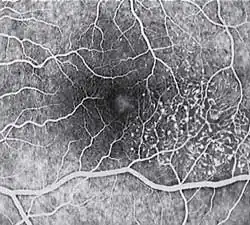

Diagnosis of MacTel type 2 may be aided by the use of advanced imaging techniques such as fluorescein angiography (which may identify an abnormal capillary pattern), fundus autofluorescence, and OCT. These can help to identify the abnormal vessels, pigment plaques, retinal crystals, foveal atrophy and intraretinal cavities associated with this disorder.

Fluorescein angiography (FA) is helpful in identifying the anomalous vasculature, particularly in the early stages of Type 2 disease. Formerly, FA was essential in making a definitive diagnosis. However, the diagnosis can be established with less invasive imaging techniques such as Ocular Coherence Tomography (OCT) and fundus autofluorescence. Some clinicians argue that FA testing may be unnecessary when a diagnosis is apparent via less invasive means.